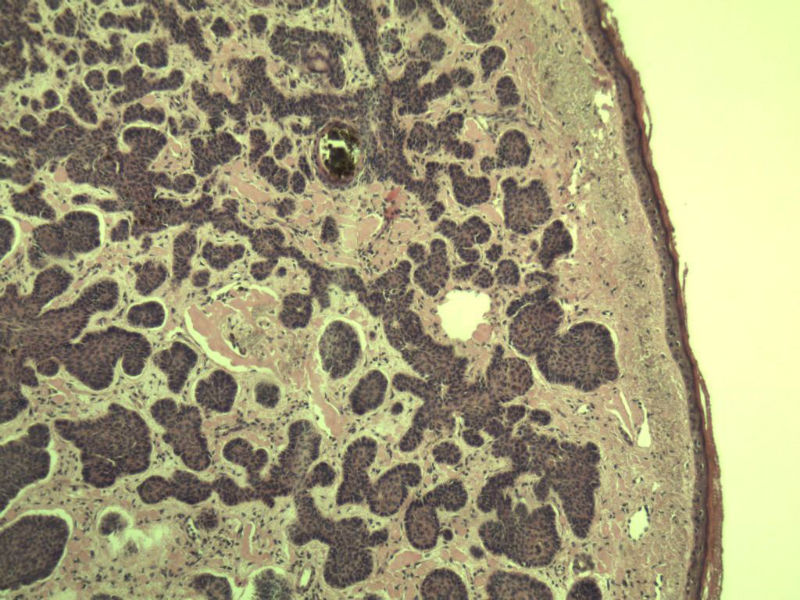

这是另外一个  75岁 男性 脸上有一直径0.8cm新生物 是鳞癌吗? 感觉细胞异型性不够大.

第二例:基底细胞癌

第二例,两种成分,1、毛发上皮瘤;2、皮内痣。

第一例考虑毛母细胞瘤,第二例考虑基底细胞癌。

第一例:毛母细胞瘤;第二例:基底细胞癌

第一例,毛发上皮瘤;第二例,基底细胞癌。

1.BCC.  2.BCC.

二基底细胞癌。

两例均为BCC